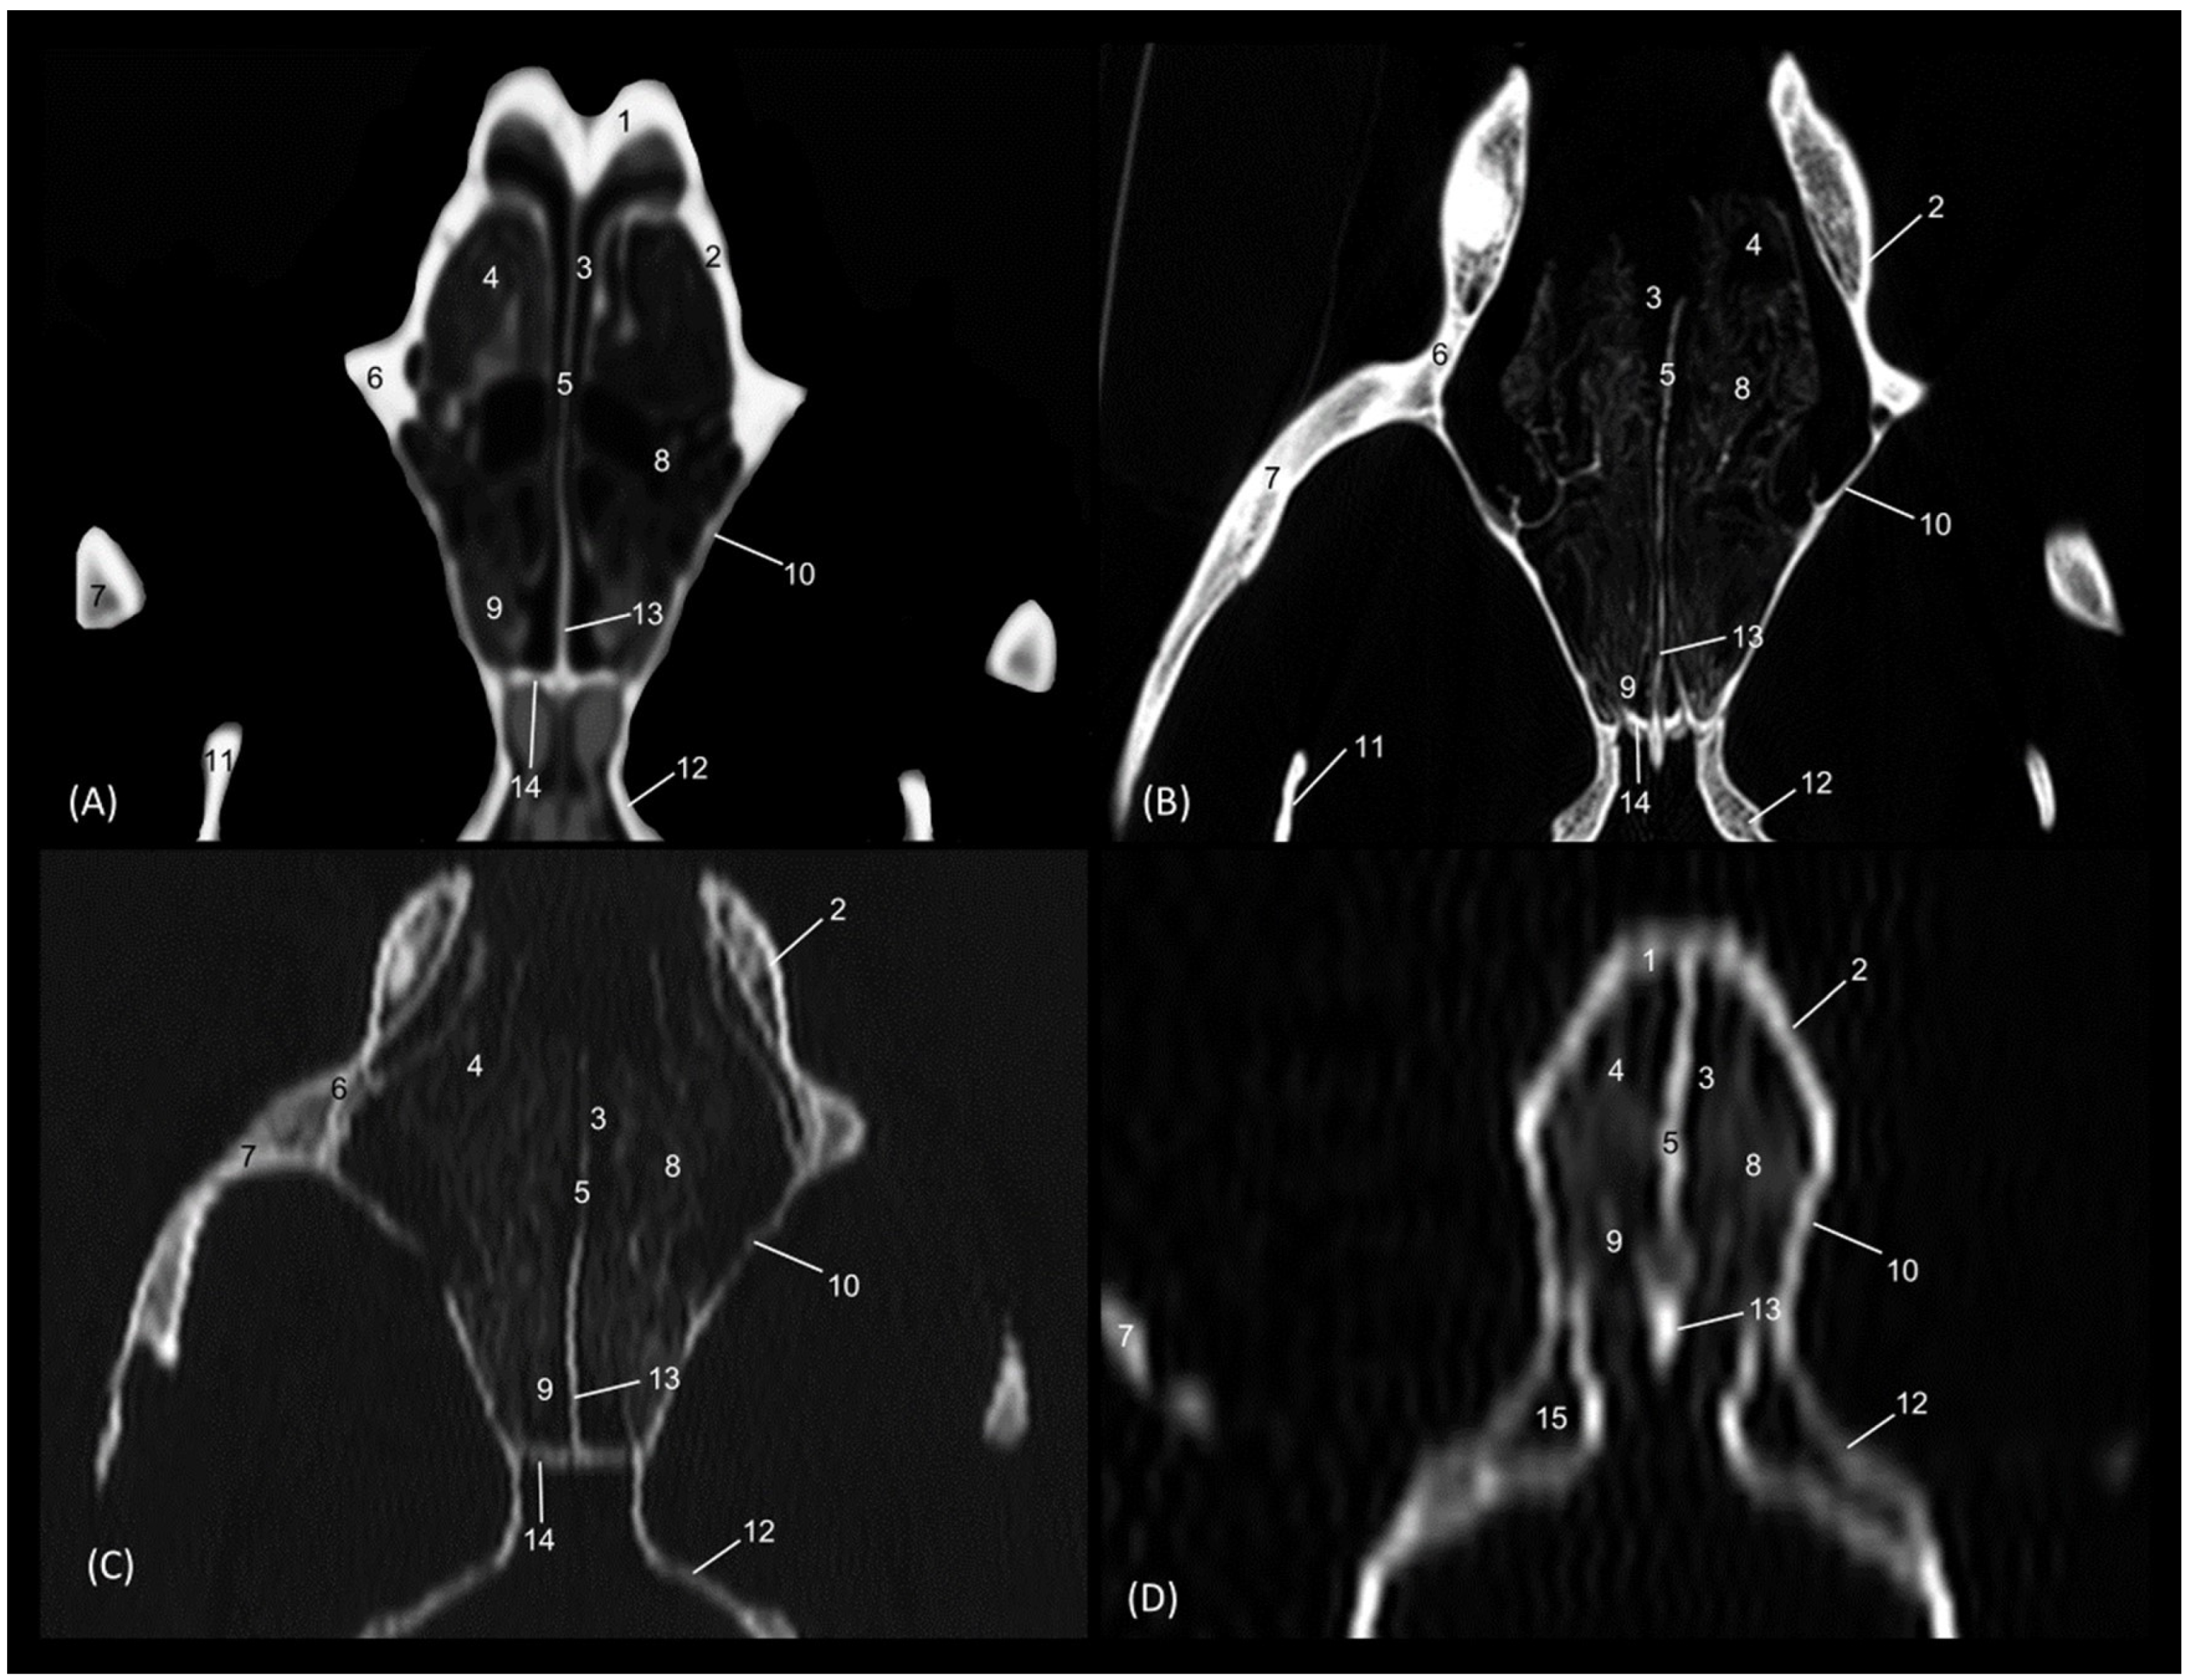

Through tomographic studies carried out on the heads of felids, 3D reconstruction models were developed using 3D MIP (Figure 27, Figure 28, Figure 29 and Figure 30) and VR (Figure 31, Figure 32, Figure 33 and Figure 34) applications. MIP reconstruction techniques allowed us to clearly visualize the internal dimension of each structure of the nasal cavity and paranasal sinuses. Sagittal, transverse, and dorsal views of the four felids were selected.

The MIP of the cheetah head is represented in Figure 29. The frontal sinus is considerably larger in this species, as is the sphenoidal sinus, which is proportionally much larger than in the other species examined.

Figure 29. OsiriX MIP CT reconstruction images of the cheetah’s head. (A) Sagittal image. Left lateral view. (B) Transverse image. Caudal view. (C) Dorsal image. Dorsal view. 1. Incisive bone; 2. Nasal bone; 3. Maxilla; 4. Frontal bone: external plate; 5. Frontal bone: internal plate; 6. Frontal bone: orbital surface; 7. Ethmoid bone: tectorial plate; 8. Ethmoid bone: cribriform plate; 9. Frontal sinus; 10. Frontal sinus: septum; 11. 1st ectoturbinate. 12. 2nd ectoturbinate; 13. 3rd ectoturbinate; 14. Dorsal nasal concha; 15. Middle nasal concha; 16. 3rd endoturbinate; 17. 4th endoturbinate; 18. Ventral nasal concha; 19. Nasal septum: ethmoid bone (perpendicular plate); 20. Nasal septum; cartilage; 21. Vomer; 22. Zygomatic bone: frontal process; 23. Sphenoidal sinus; 24. Choana; 25. Palatine bone: horizontal and perpendicular plates; 26. Presphenoid bone.

Animals 14 02609 g029

Finally, the MIP reconstruction of the domestic cat’s head is shown in Figure 30. The frontal sinus in this species, also proportionally large, deepens to more ventral levels than in the other felids. The ectoturbinates could also be clearly seen in the sagittal and transverse images. Both the path and the width of the nasopharynx (pars nasalis pharyngis) could also be observed extending caudal from the choana.

Figure 30. OsiriX MIP reconstruction images of the cat’s head. (A) Sagittal image. Left lateral view. (B) Transverse image. Caudal view. (C) Dorsal image. Dorsal view. 1. Incisive bone; 2. Nasal bone; 3. Maxilla; 4. Frontal bone: external plate; 5. Frontal bone: internal plate; 6. Frontal bone: orbital surface; 7. Ethmoid bone: tectorial plate; 8. Ethmoid bone: cribriform plate; 9. Frontal sinus; 10. Frontal sinus: septum; 11. 1st ectoturbinate. 12. 2nd ectoturbinate; 13. 3rd ectoturbinate; 14. Dorsal nasal concha; 15. Middle nasal concha; 16. 3rd endoturbinate; 17. 4th endoturbinate; 18. Ventral nasal concha; 19. Nasal septum: ethmoid bone (perpendicular plate); 20. Nasal septum: cartilage; 21. Vomer; 22. Zygomatic bone: body; 23. Sphenoidal sinus; 24. Choana; 25. Palatine bone: horizontal and perpendicular plate; 26. Presphenoid bone.